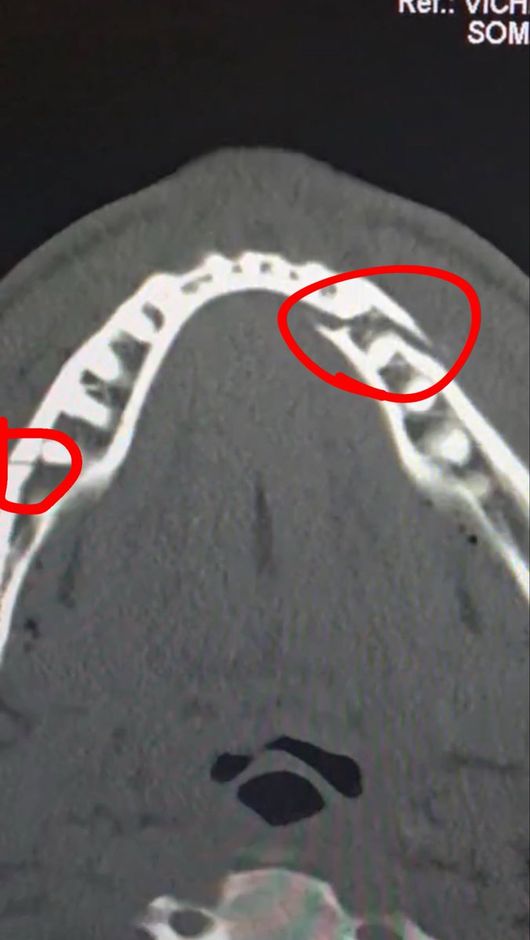

진단 결과 폴의 턱뼈는 두 곳이나 골절돼 세 동강이 난 모습이었다. 그는 곧바로 수술대에 올랐고, 티타늄 플레이트 두 개를 삽입했다. 치아도 일부 제거해 한동안 정상적인 식사도 불가능한 것으로 알려졌다.

폴은 소셜 미디어를 통해 자신의 수술 후 상태를 공개하면서 "통증이 심하지만 난 괜찮다. 턱뼈가 두 군데나 으스러졌다. 7일 동안 유동식을 먹어야 한다"라고 밝혔다. 경기를 앞두고 조슈아에게 "널 죽여버리겠다"라고 도발했던 폴이지만, 조슈아의 벽은 너무나 높았다.